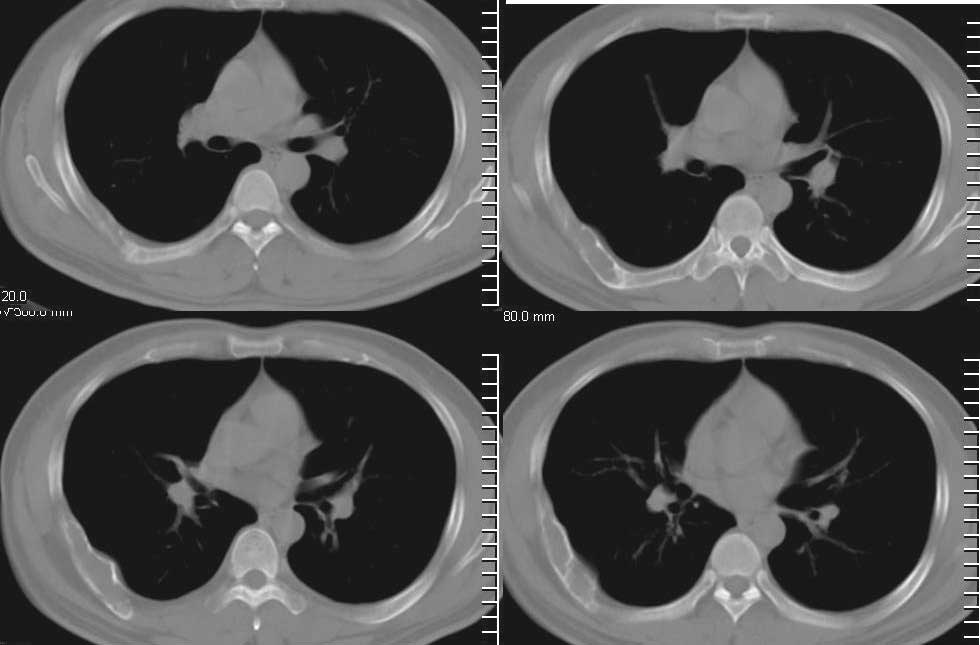

房**,38岁,间歇性胸疼2年

肋骨溶骨性破坏,皮质膨胀呈囊状,可见间隔,部分边缘硬化。考虑肋骨骨纤维结构不良。

膨胀性肋骨破坏,皮质连续。周围软组织无异常。良性占位。首先考虑骨纤。

膨胀性肋骨破坏,皮质连续,内无钙化。周围软组织无异常。良性占位。首先考虑  1骨纤  2内生性软骨瘤及骨囊肿待排

支持jiajie老师,17楼的guzhongliangddd老师整的放大图片更能明确的说明问题。

肋骨溶骨性破坏,皮质膨胀呈囊状,可见间隔,部分边缘硬化。考虑良性病变,肋骨骨纤维异常增生症可能大

膨胀性肋骨破坏,皮质连续,硬化。周围软组织无异常。良性占位。首先考虑  1骨纤  2内生性软骨瘤